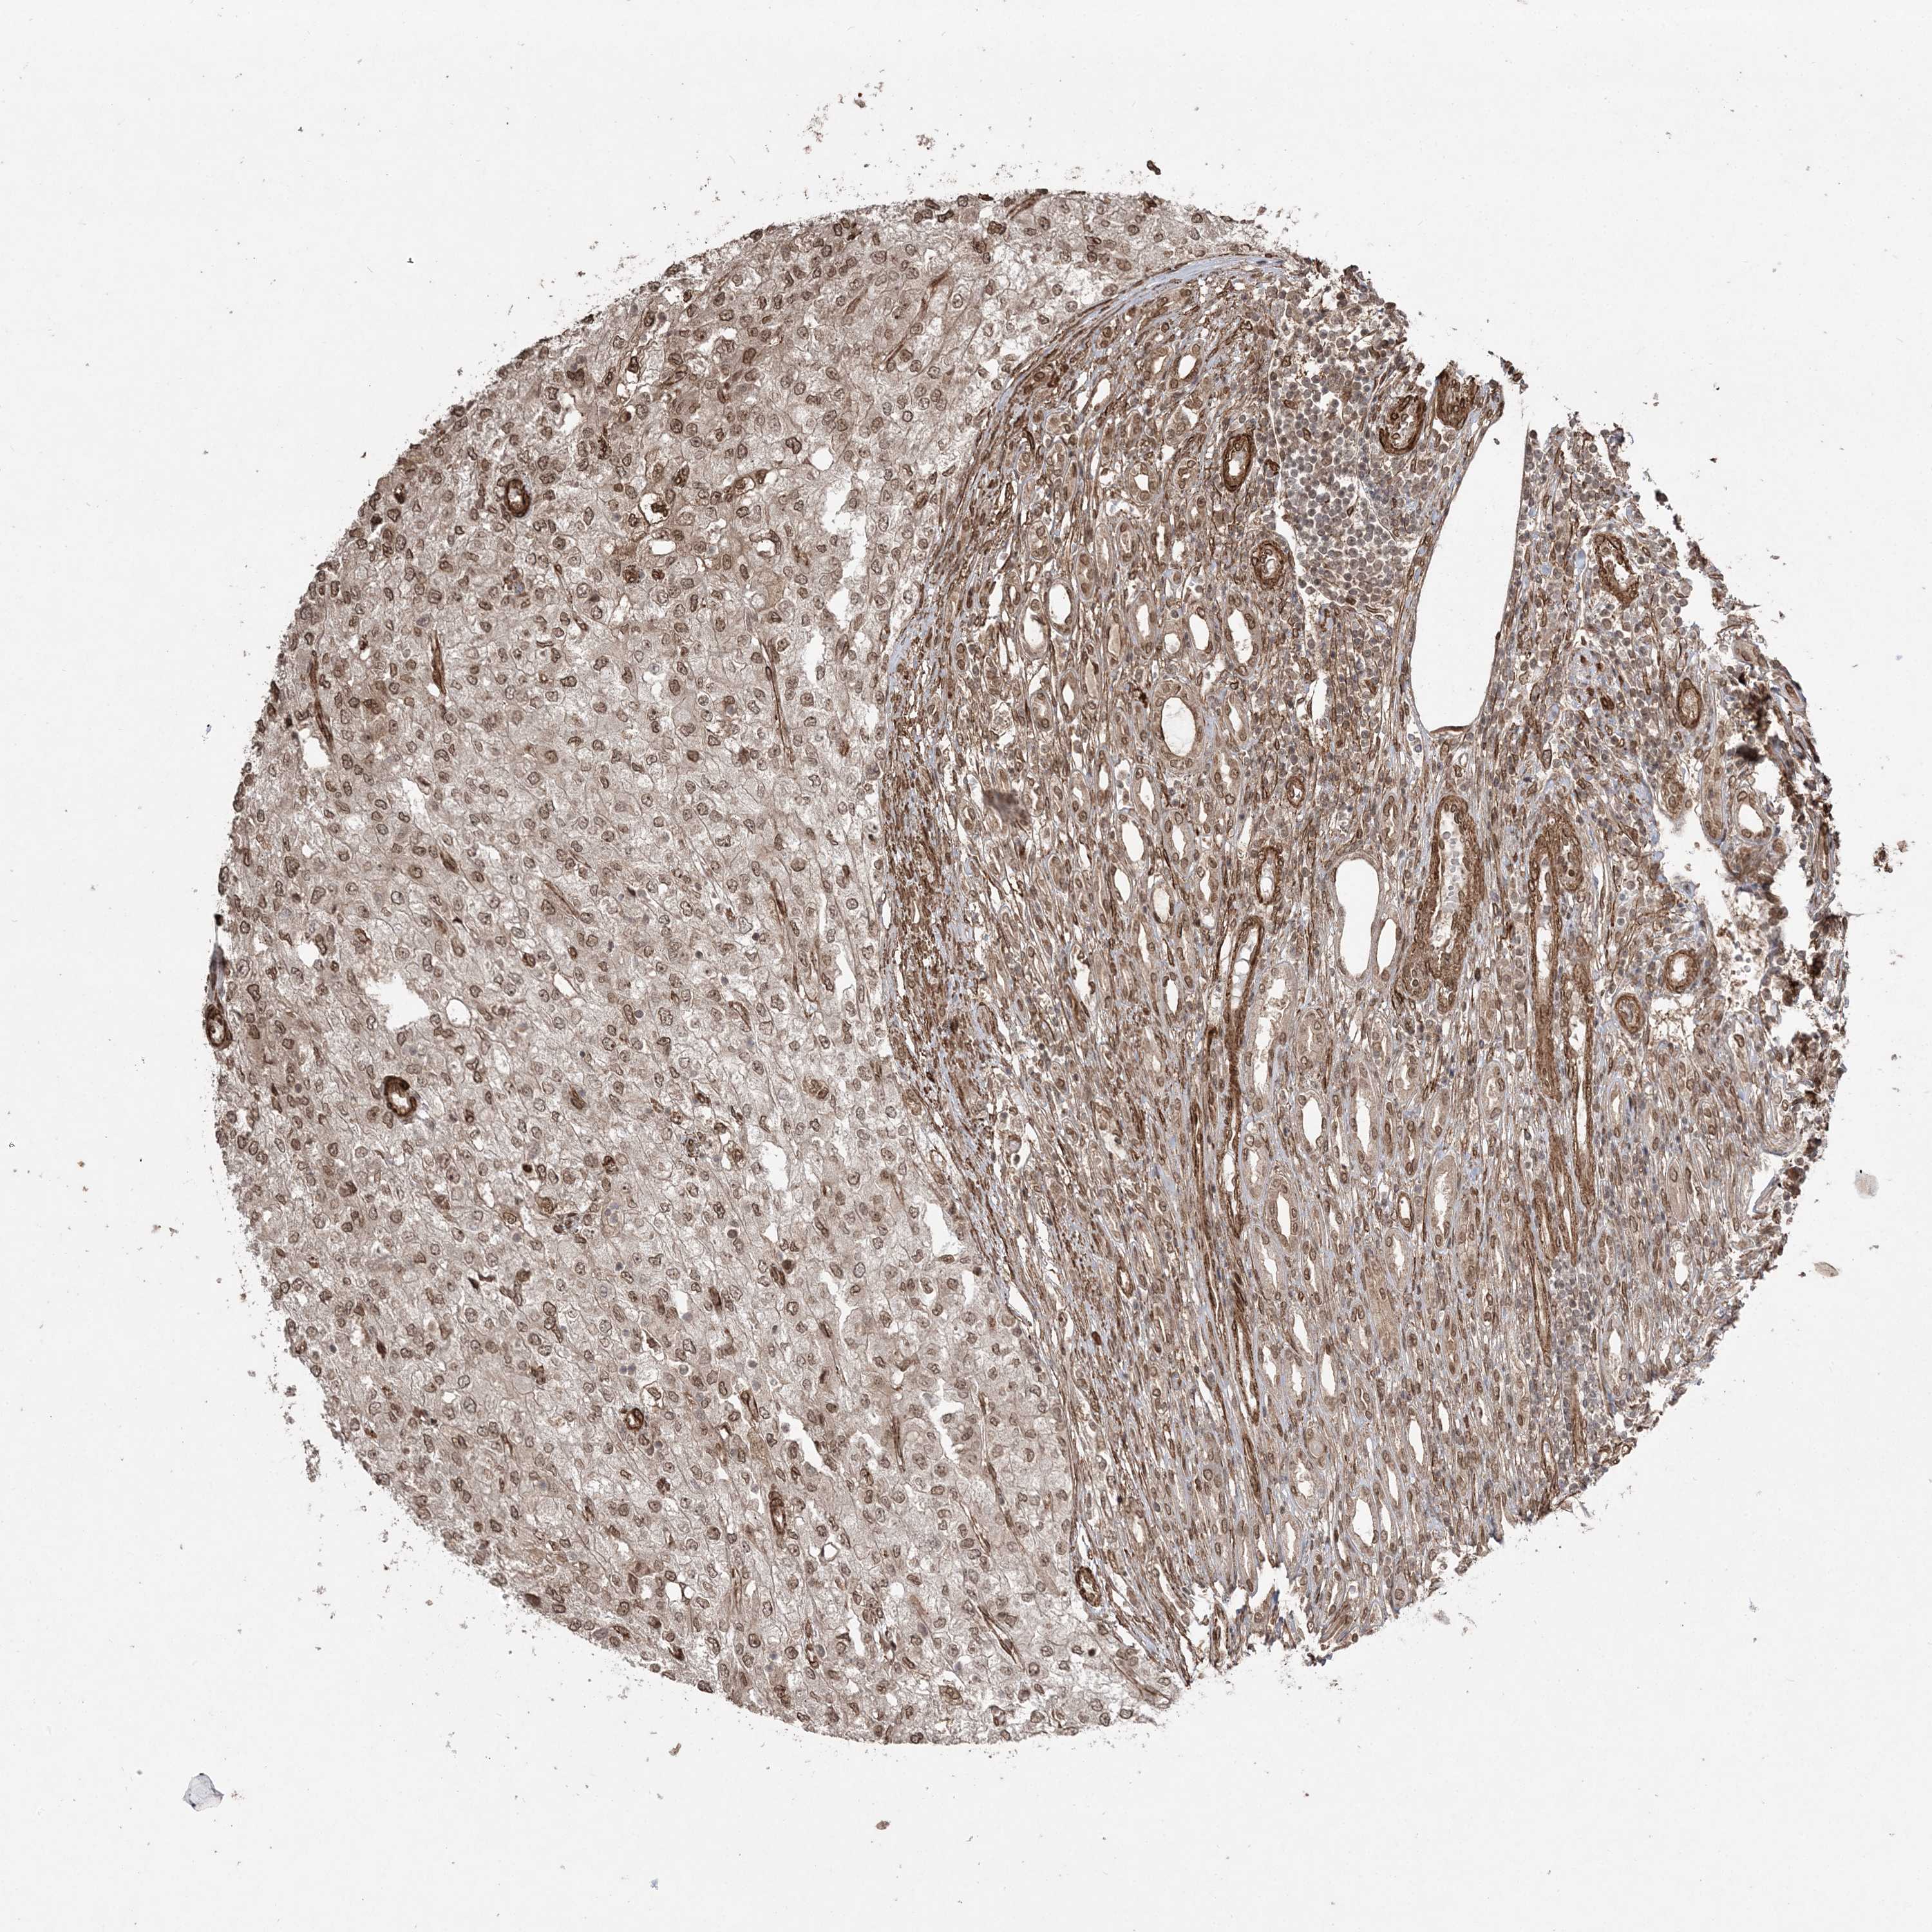

KIDNEY RENAL CLEAR CELL CARCINOMA (VALIDATION) - Interactive survival scatter ploti

The Survival Scatter plot shows the clinical status (i.e. dead or alive) for all individuals in the patient cohort, based on the same data that underlies the corresponding Kaplan-Meier plots. Patients that are alive at last time for follow-up are shown in blue and patients who have died during the study are shown in red.

The x-axis shows the expression levels (FPKM) of the investigated gene in the tumor tissue at the time of diagnosis. The y-axis shows the follow-up time after diagnosis (years). Both axes are complimented with kernel density curves demonstrating the data density over the axes. The top density plot shows the expression levels (FPKM) distribution among dead (red) and alive patients (blue). The right density plot shows the data density of the survived years of dead patients with high and low expression levels respectively, stratified using the cutoff indicated by the vertical dashed line through the Survival Scatter plot. This cutoff is automatically defined based on the FPKM cutoff that minimizes the p-score. The cutoff can be changed by dragging the vertical line or by entering a cutoff value in the square labeled "Current cut-off".

Under the Survival Scatter plot the p-score landscape (black curve; left axis) is shown together with dead median separation (red curve; right axis). Dead median separation is the difference in median mRNA expression between patients who have died with high and low expression, respectively. It is calculated as follows: median FPKM expression of dead patients with high expression - median FPKM expression of dead patients with low expression. This is intended to aid the user in visually exploring custom cutoffs and the associated p-scores and dead median separation.

Individual patient data is displayed and can be filtered by clicking on one or more of the category buttons on the top of the page. Categories describing expression level and patient information include: high, low, alive, dead, female, male and tumor stages. The scale of the x-axis can be toggled between linear and log-scale by clicking on the "x log" button. Mouse-over function shows TCGA ID, patient information and mRNA expression (FPKM) for each patient.

& Survival analysisi

Kaplan-Meier plots summarize results from analysis of correlation between mRNA expression level and patient survival. Patients were divided based on level of expression into one of the two groups "low" (under cut off) or "high" (over cut off). X-axis shows time for survival (years) and y-axis shows the probability of survival, where 1.0 corresponds to 100 percent.

ETAA1 is not prognostic in Kidney Renal Clear Cell Carcinoma (validation)

Best expression cut offi

Based on the FPKM value of each gene, patients were classified into two groups and association between prognosis (survival) and gene expression (FPKM) was examined. The best expression cut-off refers the FPKM value that yields maximal difference with regard to survival between the two groups at the lowest log-rank P-value. Best expression cut-off was selected based on survival analysis .

When clicking on this number, the vertical dashed line indicating cut-off, the interactive survival plot, and the Kaplan-Meier curve will be adjusted to show results based on the best expression cut-off.

: 11.19

Median expressioni

Median expression refers to the median FPKM value calculated based on the gene expression (FPKM) data from all patients in this dataset. When clicking on this number, the vertical dashed line indicating cut-off, the interactive survival plot, and the Kaplan-Meier curve will be adjusted to show results based on the median expression.

: N/A

Median follow up timei

Median follow up time refers to the median time (years) after diagnosis with this type of cancer, based on clinical data from all patients in this dataset.

P scorei

Log-rank P value for Kaplan-Meier plot showing results from analysis of correlation between mRNA expression level and patient survival.

N/A

5-year survival highi

5-year survival for patients with higher expression than the expression cutoff.

For melanoma and glioma, 3-year survival is shown.

5-year survival lowi

5-year survival for patients with lower expression than the expression cutoff.

TCGA RNA samplesi

RNA-seq data is reported as average FPKM (number Fragments Per Kilobase of exon per Million reads), generated by the The Cancer Genome Atlas (TCGA) .

Normal distribution across the dataset is visualized with box plots, shown as median and 25th and 75th percentiles. Points are displayed as outliers if they are above or below 1.5 times the interquartile range. FPKM values of the individual samples are presented next to the box plot.

Average pTPM 8.9

Number of samples 100